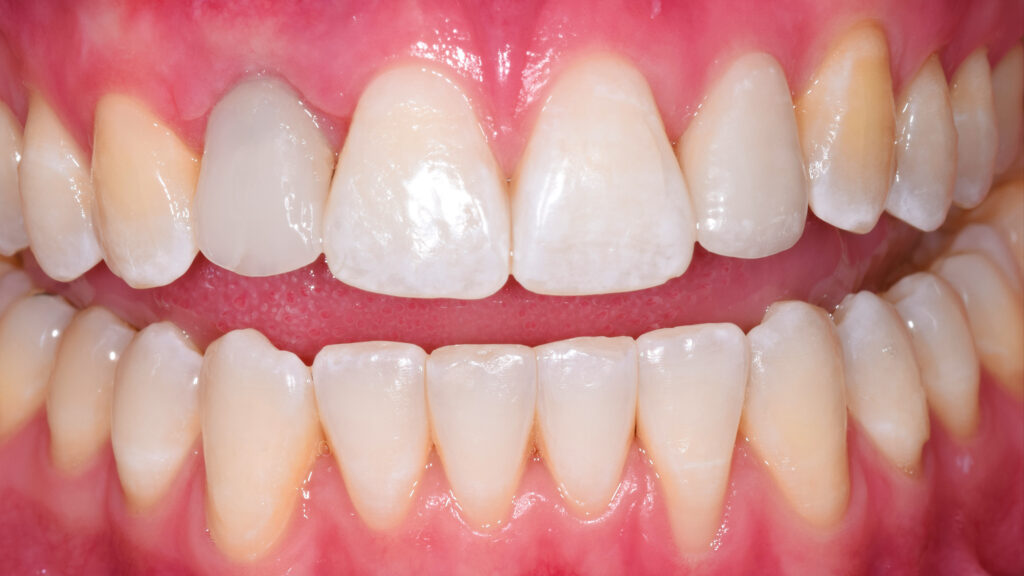

Nach der Heilung des Weichgewebes sind die arkadenförmige Kontur der Gingiva und die Papillen deutlich zu erkennen (Abb. 42 und 43). Etwa sechs Monate nach der Osseointegration und Konditionierung der Gingiva wird die Situation mit dem Intraoralscanner erfasst, um mit der Herstellung der implantatprothetischen Versorgung fortzufahren. Nach dem Aufschrauben des Scanbodys auf das Implantat erfolgt der Scanvorgang (Abb. 44). Intraoralscanner gehören zu den aufregendsten neuen Technologien in der Zahnmedizin. Die digitale Abformung bietet dem Patienten deutlich mehr Komfort. Zudem werden klinische Abläufe vereinfacht und die Kommunikation mit dem Zahntechniker verbessert. Im nächsten Schritt werden die STL-Dateien für den Modelldruck aufbereitet (Abb. 45). Vor dem Scannen der gedruckten Modelle muss das Modellanalog regio 12 eingesetzt werden. Das Modell mit abnehmbarer Gingivamaske ist für die Aufnahme des Modellanalogs durch eine Öffnung vorbereitet und besitzt im unteren Bereich des Ausschnittes eine Art Verriegelungsmechanismus (Abb. 46). Dies gewährleistet einen sicheren Presspassung und eine korrekte, automatisch zentrierte Einschubposition (Abb. 47).

Abschließend kann der Schraubenkanal mit Teflonband und Komposit verschlossen und die statische und dynamische Okklusion überprüft werden. Bei der Eingliederung einer Frontzahnimplantatkrone kommt es vor allem auf eine ästhetische Integration an. Neben der weißen Ästhetik ist die rote Ästhetik mit der Ausformung des Emergenzprofils und der Harmonie des Gingivaverlaufs wichtig. Die Restauration fügt sich ästhetisch gut in die Zahnreihe ein (Abb. 66 bis 68). Das Zusammenspiel der dentalen und gingivalen Umgebung sowie der Lippen mit der prothetischen Versorgung ergibt ein harmonisches Gesamtbild (Abb. 69). Einige Monate nach dem Einsetzen der Implantatkrone hat sich die Gingiva sichtbar gut erholt (Abb. 70).